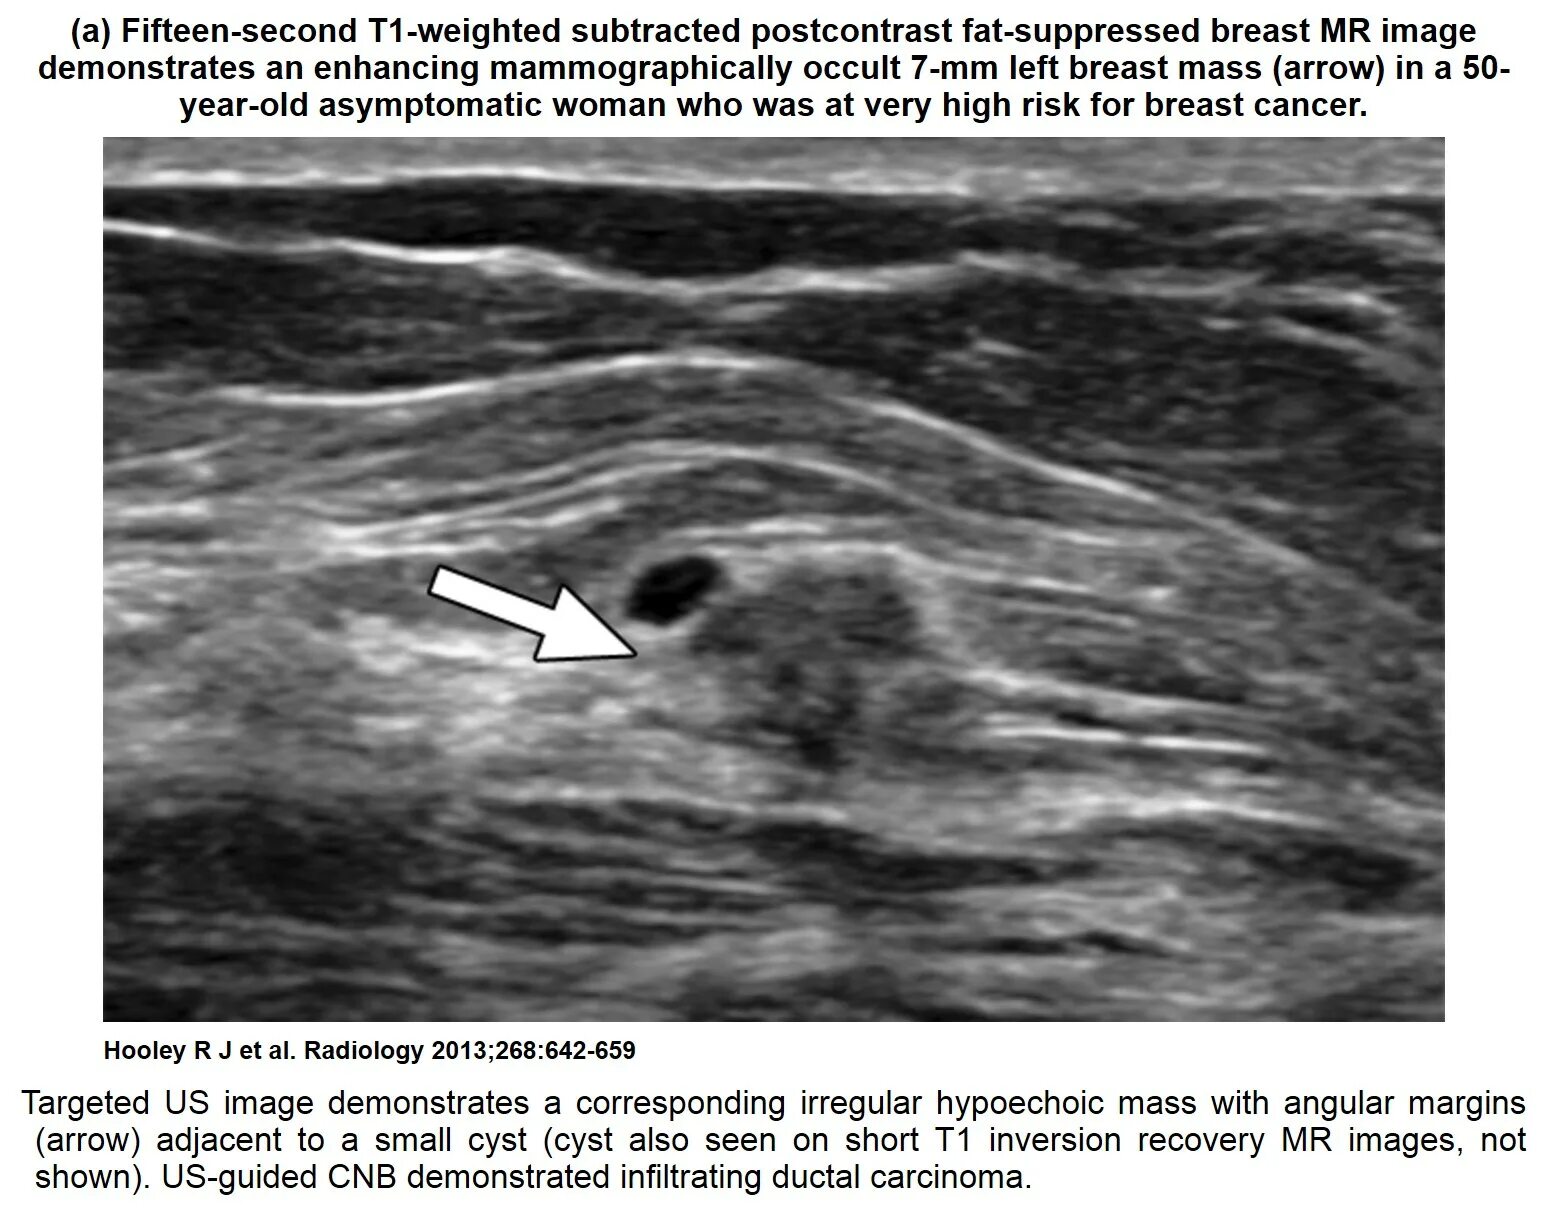

Как выглядит киста молочных желез